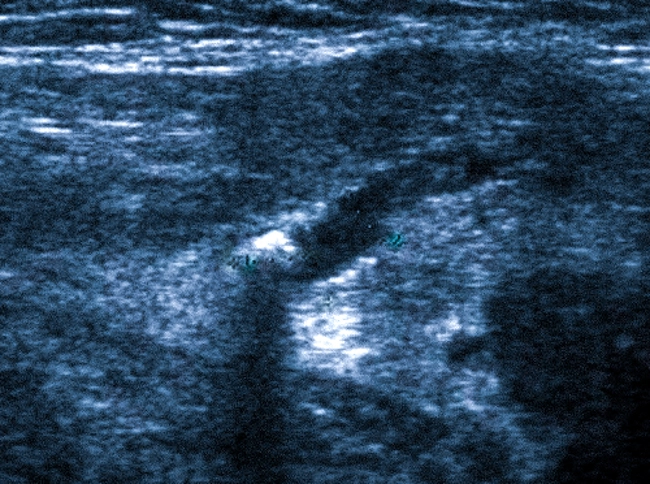

Процедура ультразвукового исследования слюнной железы

УЗИ можно пройти как в государственной клинике, так и в частном медицинском центре. Акустические волны, используемые для исследования, не приводят к изменениям в клетках, поэтому обследование абсолютно безопасно как для взрослых, так и для детей.

Во время процедуры пациент лежит на спине в кабинете УЗИ.

Специалист наносит на исследуемую область прозрачный гель, устанавливает преобразователь и наблюдает за изображением слюнных желез и окружающих тканей на экране. Для УЗИ подъязычной и подчелюстной желез может потребоваться введение специального датчика в ротовую полость. В процессе исследования вводятся индивидуальные замеры в протокол.

При выраженном воспалении пациент может ощущать дискомфорт. Обычно обследование занимает 15-20 минут. По окончании ультразвукового исследования гель удаляется, он не вызывает аллергических реакций и не оставляет следов на одежде. Результаты обследования и, при необходимости, фотографии, подтверждающие наличие патологий, предоставляются пациенту почти сразу же.